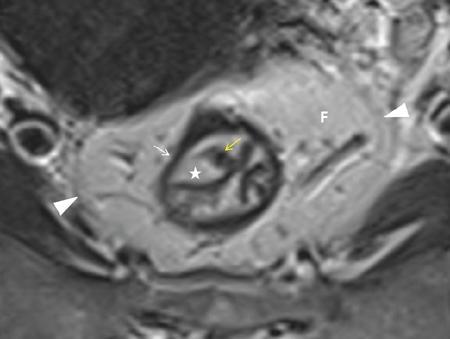

Sumit Mukhopadhyay, Saugata Sen, Aditi Chandra, Argha Chatterjee, Priya Ghosh, Anisha Gehani Cloaca is the part of hindgut caudal to the attachment of the allantoic diverticulum. It divides into a broad anterior urogenital (vesicourethral and urogenital sinus) part and a narrow posterior anorectal compartment/primitive rectum, separated by the urorectal septum. This anorectal compartment gives rise to mid rectum and lower rectum and upper part of anal canal proximal to dentate line. The peritonealized upper part of rectum develops from hindgut proximal to cloaca. The distal most part of anal canal below the dentate line develops from invaginated ectoderm known as proctodeum (Fig. 8.5.1). Initially during development, the rectum is suspended from the posterior abdominal wall by a mesentery, along with the rest of the gut. After completion of rotation of the gut, rectal mesentery fuses with the posterior abdominal wall, majority of rectum becomes retroperitoneal and hindgut mesentery is seen as mesorectum. The artery of the hindgut is inferior mesenteric artery. Anatomically, classically taken as 6 inches (approximately 15 cm), or beginning at the level of S3 vertebra. Surgically defined as 15–18 cm from anal verge (AV), thus anal canal and rectum are considered together for the purpose of surgical and radiological anatomy, though management differs in cases of rectal adenocarcinoma and anal squamous cell carcinoma (SCC). Various trials on rectal cancer neoadjuvant therapy have taken different lengths of cut-off for rectal cancer starting from AV: 9 cm, 12 cm, 15 cm or 16 cm (Table 8.5.1). Rectum continues as sigmoid colon superiorly. The point of transition between rectum and sigmoid colon is controversial. Anatomically, this is the point where sigmoid mesocolon ends, appendices epiploicae are lost and taenia coli gradually converge and disappear. There is no single transition point between these features. These features are not visible to the radiologist/endoscopist as well. Several features defining rectosigmoid junction/transition are variously accepted by different radiologists: Rectum continues as anal canal, which opens to the exterior at AV (mucocutaneous junction). Anorectal junction (ARJ) is considered to be the point at which the angle of the long axis changes, and corresponds to the upper border of puborectalis muscle. The change in axis of anal canal and rectum is well visualized on sagittal MRI. Dentate line lies along the anal crypts (the openings of anal glands), and vertical folds called columns of Morgagni extend superiorly from the dentate line. Anatomists consider the dentate line to be the landmark for ARJ, but the dentate line lies distal to the puborectal sling, and this definition is not clinically relevant. Anal canal is directed posteroinferiorly. At ARJ, the long axis of rectum changes so that it is directed anteroinferiorly. Mid rectum and upper rectum follow the sacral concavity, and the long axis of rectum is again directed posteroinferiorly. Upper rectum is frequently mobile and may not be in midline. Three incomplete folds consisting of mucosa, submucosa and circular muscles, named as Valves of Houston, are seen within the lumen of rectum during endoscopy, but these are not visualized radiologically. The middle valve is roughly at the level of anterior peritoneal reflection, and the superior most valve is at the level of rectosigmoid junction. Surgically and radiologically, rectum is divided into thirds: lower third, middle third and upper third (Table 8.5.2). Most commonly, this division is according to distance or length from AV. Lower third is 0–5 cm, middle third is 5–10 cm, upper third is 10–15 cm from AV (Fig. 8.5.6). Some radiologists define low rectum as 6 cm or less from AV, mid rectum as 7–11 cm and upper rectum as 12–15 cm. The justification of defining low rectum as 6 cm or less from the AV is that, management of most of the tumours at this location suffers from surgical challenges due to tapering of mesorectum and proximity of other pelvic structures. These tumours have a higher rate of CRM positivity, abdomino-perineal resection (APR) and permanent stoma, higher rates of recurrence and mortality, poor function of stoma after sphincter preservation. Another way of defining low rectum, surgical management of which differs from the upper two-thirds, is the portion lying distal to the proximal origin of levators at pelvic side wall. This definition was provided by the English National Low Rectal Cancer Development Programme (LOREC) and is best visualized in the coronal plane by a line joining proximal origins of levators at pelvic side walls (Fig. 8.5.7). ARJ is an important landmark in the management of rectal cancer. Distance between lower border of the tumour and ARJ is important for treatment planning. ARJ is defined as the point at which puborectalis fuses with the levator muscles, and the long axis of rectum changes from anteroinferior to posteroinferior at this point. Its upper extent begins few centimetres above the dentate line, and its length varies from 2–5 cm from AV. Histologically the proximal end of the anal canal is the point at which the columnar epithelium of the rectum becomes the transitional epithelium. Anal canal mucosa has several longitudinal columns, known as anal columns, which end at the dentate line. Below the dentate line the mucosa is smooth and transitions into skin at AV. Approximately at the level of dentate line, the internal anal sphincter (IAS) ends, and the smooth mucosa leads to the intersphincteric plane, distal to which the external anal sphincter extends up to the AV (Fig. 8.5.8). Upper third of rectum is anteriorly covered by peritoneum. Peritoneal covering gradually widens superiorly till it is covered by peritoneum on all sides at the level of sigmoid colon. The exact level of peritoneal reflection varies between individuals, and is quite often seen in axial and sagittal MRI. In axial T2-weighted MRI, a thin hypointense layer with V-shaped attachment to anterior rectal wall is seen representing the anterior peritoneal reflection. This is known as the ‘sea-gull’ sign. Mesorectum and mesorectal fascia (Fig. 8.5.10): lower two-thirds are surrounded by extraperitoneal fat and connective tissue known as mesorectum, which contains lymph nodes, nerves and blood vessels (descending branches of superior rectal artery and corresponding veins). Mesorectal fat is contained within a thin layer of fascia, known as mesorectal fascia (MRF). MRF separates mesorectal fat from extra mesorectal tissues of the pelvis. A relatively avascular plane of areolar tissue lies between MRF and parietal pelvic fascia, facilitating surgery. Importance: Assessment of structures within mesorectum is important for staging and prognostication of rectal cancer. Mesorectal node involvement is N disease. Tumour extension within mesorectal vessels is known as extramural vascular invasion (EMVI) and is thought to be associated with higher chances of vascular dissemination and distant metastases. MRF forms the boundary of the surgical excision plane in total mesorectal excision (TME) – the standard surgery for rectal cancers at present. It is important to understand the various fascial reflections of the pelvis in order to understand pathways of disease spread. The plane between the MRF and the pelvic fascias is the surgical plane. Posteriorly, covering the sacrum, presacral venous plexus and hypogastric nerves, lies the presacral fascia. It fuses with MRF inferiorly at the level of levator ani muscle. The space between presacral fascia and MRF is known as the retrorectal/rectosacral/pelvirectal space, and that between the sacrum and presacral fascia is the presacral space. The presacral fascia continues laterally as the parietal pelvic fascia which covers the lateral pelvic wall. It has two lamellae which encase the pelvic visceral nerves as they course forward from the sacrum to the anterior pelvic organs. The rectosacral fascia/Waldeyer fascia, called as rectosacral ligament by anatomists, is a thickening arising from presacral fascia and running forward to meet the MRF. This divides the rectosacral space into a superior and an inferior compartment, communicating with each other. In males, anteriorly, between the rectum and prostate-seminal vesicles, lies the rectoprostatic fascia/Denonvillier fascia. It is difficult to distinguish from the closely related MRF, and carries the hypogastric nerve and vascular branches to the prostate and male genital organs. In females, anterior to the MRF, lies the rectovaginal septum. According to most views, this septum consists of two layers. The anterior layer corresponds to Denonvillier fascia, and extends from the pelvic floor to the posterior wall of vagina and uterus. The posterior layer is in close relation to the MRF, runs from the pelvic diaphragm and ascends to the peritoneal reflection before fusing with the rectal wall. The lateral rectal ligaments are controversial structures as they are not visualized by imaging and may not carry important structures such as nerves and vessels. However, in some cases, the middle rectal artery may run through them and the accompanying lymphatics may provide a pathway between mesorectal and extra mesorectal lymph nodes. In females, the pelvic floor may be considered to have three compartments, anterior compartment containing bladder and urethra, middle compartment containing the vagina and the posterior compartment containing the rectum. These compartments are supported by the endopelvic fascia and levator ani muscle. The levator ani has several compartments, of which the two most important ones are the iliococcygeus and puborectalis. The iliococcygeus starts as the same fibres as the EAS, and then fans out as a sheet to insert at the pelvic sidewall at the tendinous arch. Posteriorly these fibres fuse in the midline to form the levator plate/raphe. The pubococcygeus and puborectalis are considered together as pubovisceralis muscle. It inserts lateral to the symphysis pubis anteriorly, and forms a sling around the rectum, pulling it anteriorly. Components of the levator ani can be identified in T2-weighted MR images. In males, there are two compartments, anterior containing bladder, urethra, prostate and seminal vesicles and the posterior compartment containing the rectum. Pubococcygeus consists of pubourethralis and puborectalis in males. In sagittal images, the pubococcygeal line is an important reference line, drawn from the inferior border of symphysis pubis to the last joint of the coccyx, representing the level of pelvic floor. The H line is drawn from the inferior aspect of the symphysis pubis to the posterior wall of the rectum at the level of ARJ. This represents the anteroposterior width of the levator hiatus, and upper limit of normal is 5 cm. The M line is the vertical descent of the levator hiatus, drawn as a perpendicular line dropped from the pubococcygeal line to the posteriormost aspect of the H line, and should measure maximum 2 cm. The angle of the levator plate and the pubococcygeal line is also measured. In axial images, the entire normal levator is of uniform thickness and homogeneous low signal intensity. Coronal images show intact iliococcygeus muscle which is convex upwards. The upper half of the anal canal proximal to the pectinate line, the IAS, the conjoint longitudinal coat and the rectum drain lymph upwards into the mesorectal nodes (Fig. 8.5.11) and then lymphatics follow the superior rectal artery into the inferior mesenteric group of lymph nodes. The lymph from these nodes is carried by the intestinal lymph trunk(s). Anal canal below the dentate line along with the EAS drains to the superficial inguinal nodes. Lymphatic vessels also travel with the median sacral artery and drain the puborectalis muscle before finally joining the internal iliac lymph nodes. The internal iliac lymph nodes drain into pre-aortic and paraaortic (lumbar) lymph nodes and efferents from the nodes form the lumbar trunks. The intestinal trunks and the lumbar trunks enter the abdominal confluence of the lymph trunks at the level of the L1–L2 vertebrae, called the cisterna chyli, and then ascend as the thoracic duct. The pelvic lymph nodes lying outside the mesorectum are termed as ‘extra mesorectal lymph nodes’. Above the dentate line: blood supply is from the superior rectal artery, which originates from the inferior mesenteric artery, a branch of abdominal aorta. Superior rectal artery passes in the sigmoid mesocolon and divides into two branches behind the rectum at the level of S3 sacral segment. The superior rectal artery ends in the anal columns by forming a rich vascular plexus/anastomosis with the branches of inferior rectal artery. Blood returns via the superior rectal veins into the inferior mesenteric vein, which drains into the splenic vein and eventually into the portal venous system. Below the dentate line, the inferior anal canal obtains its blood supply from the inferior rectal artery, which is a branch of internal pudendal artery, originating from the anterior division of internal iliac artery. Blood returns via the inferior rectal vein, which drains into internal pudendal veins, internal iliac veins and ultimately into the inferior vena cava (systemic circulation). Thus anal canal is a site of portosystemic anastomosis. Due to the venous anastomoses that occur in the anal canal and the backup of blood flow into the rectal veins, haemorrhoids may be present in patients with portal hypertension. A small part of muscular wall of rectum and anal canal is also supplied by median sacral artery, a direct branch of abdominal aorta arising at the bifurcation of aorta. Nerve supply: The inferior hypogastric plexus lies laterally on the surface of MRF on both sides. It receives sympathetic nerve fibres from the superior hypogastric nerves and parasympathetic ‘nervi erigentes’ from the laterally situated sacral nerves (S2–S4). Laterally, inferior rectal branches of the pudendal nerves and internal pudendal arteries cross the ischio-anal fossa to supply the external sphincter and anal mucosa. T2-weighted small FOV images reveal the layers of rectal wall and details of perirectal soft tissue and pelvic floor most accurately. For adequate assessment of the integrity and involvement of different layers, axial images are needed, which should be obtained perpendicular to the axis of the rectum in that segment. Angle of acquisition should be altered according to the change in axis of rectum (Fig. 8.5.12). The layers of rectal wall from inside to outside are (Fig. 8.5.10): When examining the anorectum with a radial scanning echoendoscope, the internal and EASs can be seen as two distinct rings. The inner hypoechoic ring of tissue represents the IAS the outer hyperechoic tissue ring represents the EAS. The thickness of normal IAS is 2–3 mm, and for EAS: 7–9 mm. The IAS becomes thicker and more hyperechoic with age, while the EAS tends to become thinner with age. Endoscopically, rectum begins at the dentate line and extends to 15–20 cm from the AV. The normal five-layer appearance of rectal wall in EUS is as follows: Imaging in the rectum and anal canal region is mainly for staging of tumours. The most common neoplasm of this region is rectal cancer and preoperative imaging evaluation is required not only for staging early and advanced disease but also for assessing response to treatment and for surgical planning. The techniques described here will mainly pertain to rectal and anal neoplasms. Plain radiographs have a limited role in the evaluation of rectal neoplasms. Primarily, it may be used as a modality in the emergency setting when patients come with constricting colorectal strictures causing large bowel obstruction. Radiographs of the abdomen in supine and erect positions are performed to look for features of bowel obstruction, air-fluid levels and free air under the domes of diaphragm in case of perforation, respectively. Conventional luminal contrast study is now obsolete for diagnosis of tumours in the rectum and anal canal and have been replaced by cross-sectional imaging. Sinogram studies with diluted iodinated contrast have been performed to detect extent of rectal fistulae. Endorectal Ultrasound (ERUS) can differentiate between the layers of the rectal wall and helps detect and stage tumours within the different layers of the rectum. ERUS can view the rectal mucosa in 360 degrees. The layers visualized include rectal mucosa, muscularis mucosa, submucosa, muscularis propria and area between the muscularis propria and perirectal fat. The role of ERUS in rectum is primarily in staging and in posttreatment surveillance of rectal adenocarcinoma. Staging of early tumours requires an ERUS due to its superior diagnostic performance for differentiating T1 from T2 tumours in comparison to other cross-sectional imaging modalities like MRI. As far as surveillance is concerned, endoscopy is mandated as it can detect early asymptomatic recurrences which improves overall survival (OS). This is substantiated by multiple recent meta-analyses in literature. Hence, even for patients on ‘watchful waiting’ as a treatment option after chemoradiotherapy, it is imperative to perform a DRE, EUS, CEA and correlate the findings with restaging MRI. The various recommendations for postoperative surveillance for rectal cancer using endoscopy are enumerated in Table 8.5.3. ASCO: American society of clinical oncology; ESMO: European society for medical oncology; NCCN: National comprehensive cancer network; USMSTF: United States Multi-Society Task Force. Drawbacks include heterogeneity in operator skill and operator dependency as well as inability to pass stenosing lesions. Poor depth of penetration of the probe results in reduced visualization of the mesorectal fat, limited assessment of pelvic side walls and EMVI and reduced diagnostic accuracy for asserting involvement of CRM. Multidetector CT (MDCT) is the primary imaging modality used for rapid evaluation of not only bowel pathologies (luminal or mural) but also for evaluation of surrounding structures such as vessels, lymph nodes and mesentery. The ability to obtain high-quality clinical images through multiplanar reconstructions make it one of the most robust examinations for the initial evaluation of most bowel related pathologies. A routine abdominal CT scan would include acquiring a noncontrast axial image, followed by a portal phase image (at 70–90 seconds). However, for more detailed evaluation of solid organs, a general imaging dataset would include an unenhanced CT, followed by arterial phase (20–30 seconds), portal venous phase (70–90 seconds) and a delayed phase at 3 minutes. Many centres around the world omit the noncontrast scan to reduce radiation exposure. Lesions such as large tumours, pelvic nodes, collections and diverticulosis can be detected by contrast-enhanced CT. CT provides a more holistic evaluation and demonstrates possible complications of tumours such as obstruction, transition point and perforation that may not be clinically evident. However, accurate detection and staging of tumours in the rectum is better performed by MRI. Like TRUS, MRI can depict the layers of the rectal wall with high resolution, especially when performed at 3 Tesla and with an endorectal coil. Although use of endorectal coils may provide improved diagnostic accuracy for T stage as compared with phased-array coils alone, it is known that endorectal coils increase patient discomfort and may account for increasing motion artifacts. Insertion of such coils is also not possible in case of stricturous lesions. Performance of high-resolution imaging using phased-array MRI coils at 1.5 or 3 Tesla, as was used in multicentre trials was excellent. MRI technique and image quality play a critical role in evaluation of rectal cancers, and accuracy is dependent on obtaining high-resolution images that are perpendicular to the plane of the tumour. Particular note is to be made whether the tumour is mucinous or nonmucinous as the former have worse prognosis and higher tendency to metastasize. For technical aspects of MRI, it is recommended by ESGAR that bowels and bladder are emptied. Rectal distension is not indicated as it stretches out the CRM. Minimum slice thickness for such scans is 3 mm. DWI is essential for both primary staging and restaging. Microenemas may be considered to remove air from the rectum and reduce artifacts in DXI sequence. High-risk MRI features for distant metastases include EMVI, mesorectal tumour depth >5 mm, T4 stage, involved circumferential resection margin (CRM). In addition to initial staging prognostic features, MRI also helps in assessing response to neoadjuvant therapy which is also an indicator of survival and chances of recurrence. MRI is sensitive in detecting the presence of lymph nodes but remains nonspecific for differentiation malignant from benign nodes with high diagnostic certainty owing to the presence of micrometastasis even in small-sized nodes (up to 5 mm). Contrast administration is not recommended. Drawbacks of MRI include reduced diagnostic accuracy for identifying early rectal T1 and T2 tumours, and to sometimes differentiate T2 from early T3 lesions. Increased scan times in the elderly and cost may also be constraints in some settings. Virtual colonoscopy can help in identifying primary and synchronous colonic lesions. CT Colonography (CTC) is beneficial after incomplete colonoscopy (due to nonpassable stricture) to evaluate the remainder of the colon. CTC is advocated as a screening test for colonic polyps and colon cancer in vulnerable populations. It has a sensitivity of 93% and a specificity of 97% for detecting polyps >1 cm. MRI scores over all modalities in the local staging of rectal neoplasms. The more common application of PET-CT is in identifying nodal and distant metastases in rectal adenocarcinoma, melanoma and lymphoma. Limitations of PET include poor sensitivity in detecting small (<10 mm) colonic lesions and decreased fluorine-18-2-fluoro-2-deoxy-D-glucose uptake by mucinous tumours. For rectal melanoma, MRI may be performed along with a whole body PET-CT scan for regional and overall staging. Rectal lymphoma does not require local staging and a whole body PET-CT is generally acceptable as the imaging modality of choice. MRI is the imaging modality of choice due to better delineation of the extent and involvement of the anal sphincters. The inguinal nodes are regional nodes in anal cancer and this region is covered in the scan. The most common rectal tumour is rectal cancer. It is also one of the most common malignant neoplasms and the second most frequent cancer occurring in the large bowel. Majority of the patients are in the fifth to seventh decade. However, the incidence of rectal cancer has been on a rise in the younger population. Adenocarcinoma is the commonest histopathologic type of rectal cancer. Other than adenocarcinoma, several other neoplastic lesions also occur in the rectum, but are relatively uncommon (Table 8.5.4). Diagnosis of rectal cancer begins with physical examination/DRE followed by colonoscopy/sigmoidoscopy and biopsy from the mass (see figure below). If malignancy is confirmed on histopathological examination, imaging for staging is ordered (Fig. 8.5.14). MRI is the preferred method for locoregional staging. During staging of early tumours, ERUS also plays an important role. Majority of the guidelines (SAR and ESGAR) accept MRI as the modality of choice for locoregional staging and restaging after neoadjuvant treatment. CT thorax and abdomen is performed for metastatic evaluation. PET-CT is not routinely recommended in metastatic evaluation. ESMO guidelines outline the following indications for PET-CT: (1) If carcino-embryonic antigen (CEA) is high on presentation (2) Extensive EMVI. MRI of the liver may be recommended to evaluate any suspicious or equivocal lesions that are detected on CT scan. Therefore routinely pelvic MRI for locoregional evaluation and CT thorax and abdomen for metastatic evaluation is performed (Table 8.5.5). Based on the investigations, the rectal cancer is staged according to the latest AJCC classification (Table 8.5.6). T0 No evidence of primary tumour Tis Carcinoma in situ T1 Tumour invades submucosa T2 Tumour invades muscularis propria T3 a b c d Tumour invades subserosal tissue and perirectal tissue a <1 mm b 1–5 mm c >5–15 mm d >15 mm T4 a b Tumour invades peritoneum or other organs Tumour penetrates visceral peritoneum Tumour invades other adjacent organs or structures NX Regional lymph nodes cannot be assessed N0 No regional lymph node metastasis N1 a b c Regional lymph node metastasis (1–3 nodes) 1 lymph node 2–3 lymph nodes Tumour deposits in subserosa, mesentery/nonperitonealized perirectal tissues (cannot be differentiated from nodes on imaging) N2 a b Regional lymph node metastasis (>4 nodes) 4–6 node >7 nodes M0 No distant metastasis M1 a B c Distant metastasis Metastasis in one (1) organ Metastasis in more than one organ Metastasis to the peritoneum with/without other organ involvement Once the diagnosis is confirmed and staging investigations are completed, management is usually decided in multidisciplinary team meetings consisting of Surgeon, Radiation oncologist, Medical oncologist, Pathologist and Radiologist. The treatment protocols differ in the United States and Europe (Fig. 8.5.15). The different types of rectal surgeries are enumerated in the Table 8.5.7 and depicted in Fig. 8.5.16. Concept of use of neoadjuvant short course RT, long course RT with chemotherapy and chemotherapy only is a rapidly evolving field. Radiologist should be aware of the protocol used in their institution. A subset of patients (10%–23%) was found to have complete pathological response (pCR) in the postsurgical pathological specimen. There is significant evidence of prediction of pCR on presurgical MRI. Considering the ability of MRI in prediction of pCR, Prof. Habr-Gama and her group suggested the possibility of organ preservation in these patients. Hence ‘watch and wait’ policy came into vogue. In the subgroup where MRI predicts complete response, surgery can be avoided and patients may be followed up every 8–12 weeks using DRE, proctoscopy/sigmoidoscopy and MRI. Both T2W and DWI are used in MRI for prediction of complete response as well as for follow-up for prediction of recurrence. Close follow using the above-mentioned protocol ensures early detection of recurrence and hence treatment. Thus, MRI plays an important role in personalized treatment of rectal cancer. MRI plays an important role in rectal cancer management: During initial staging MRI helps in: In restaging after NACT, MRI helps in: Therefore good-quality high-resolution rectal MRI is required for accurate locoregional staging. Technique and protocol of MRI is summarized in the Tables 8.5.8 and 8.5.9. 1.5T-3.0T magnet strength High resolution T2w sequences Small FOV images Axial and coronal images – parallel and perpendicular to the rectal tumour For low rectal tumours coronal images –perpendicular to the anal canal

MRI anatomy